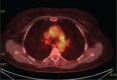

Results: Of the 160 IgG4-RD patients in this cohort, 36 (22.5%) had large-vessel involvement. The mean age at disease onset of the patients with large-vessel IgG4-RD was 54.6 years. Twenty-eight patients (78%) were male and 8 (22%) were female. Thirteen patients (36%) had primary IgG4-related vasculitis and aortitis with aneurysm formation comprised the most common manifestation. This affected 5.6% of the entire IgG4-RD cohort and was observed in the thoracic aorta in 8 patients, the abdominal aorta in 4, and both the thoracic and abdominal aorta in 3. Three of these aneurysms were complicated by aortic dissection or contained perforation. Periaortitis secondary to RPF accounted for 27 of 29 patients (93%) of secondary vascular involvement by IgG4-RD. Only 5 patients demonstrated evidence of both primary and secondary blood vessel involvement. Of those treated with rituximab, a majority responded positively.

Conclusions: IgG4-RD is a distinctive, unique, and treatable cause of large-vessel vasculitis. It can also involve blood vessels secondary to perivascular tumefactive lesions. The most common manifestation of IgG4-related vasculitis is aortitis with aneurysm formation. The most common secondary vascular manifestation is periaortitis with relative sparing of the aortic wall. Both primary vasculitis and secondary vascular involvement respond well to B cell depletion therapy.